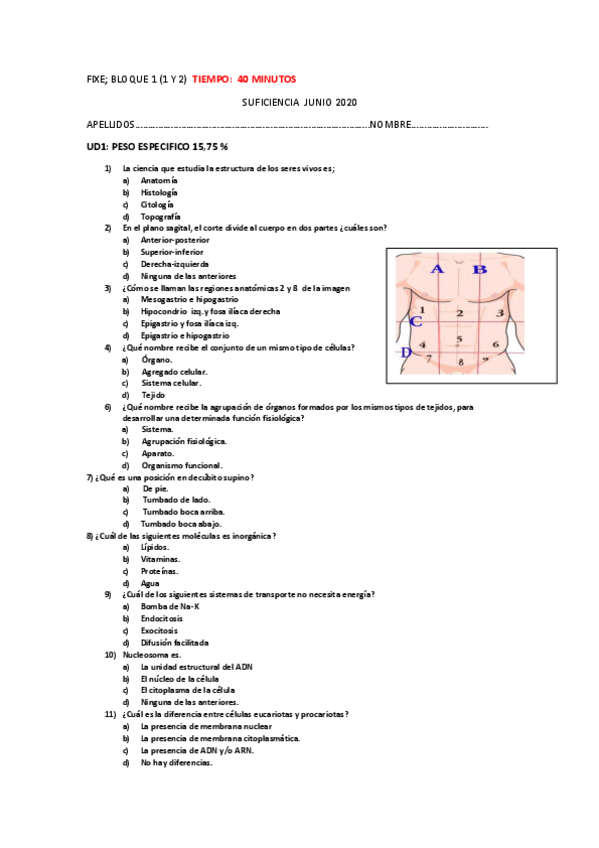

Fixe

He publicado nuevos apuntes de Fisiopatología general: Fixe